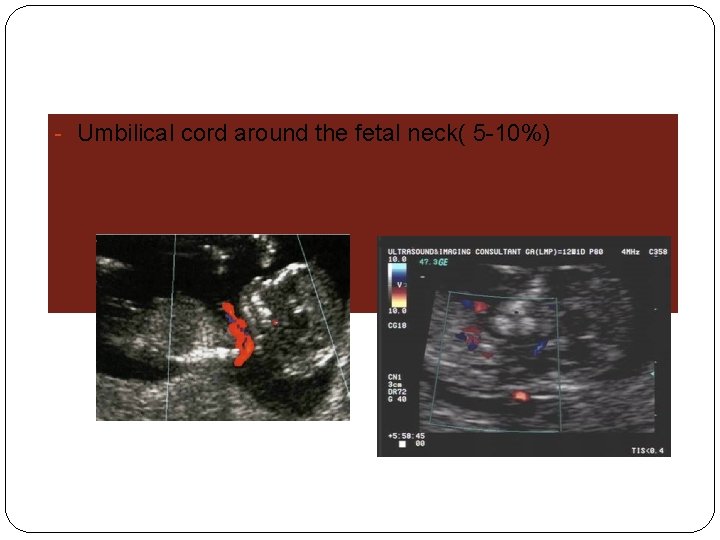

- Umbilical cord around the fetal neck( 5 -10%)